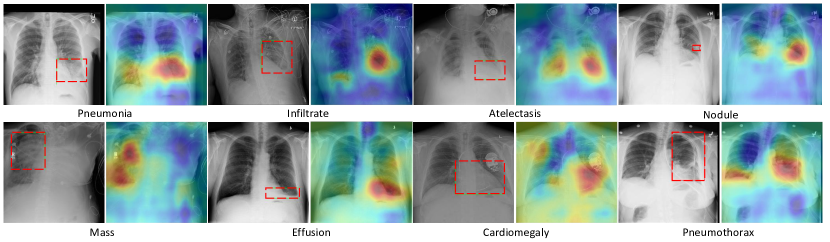

Refer to caption

Figure 1. Examples of chest X-rays of eight thoracic diseases and associated lesion regions from ChestX-ray14 (Wang et al., 2017). The regions were annotated as red bounding boxes by radiologists. The bounding boxes were only used for evaluation.

Figure 4. The proposed method localizes the areas of the X-ray that are most important for making particular pathology classification. We can see that the localized areas are very close to the corresponding bounding boxes.

4.4. Localization of Lesion Regions

In Fig.4, we produce heat map to visualize the most indicative pathology areas on X-rays from evaluation subset, interpreting the representational power of network. Heat maps are constructed by computing the average of class-wise features after pooling along the channel dimension (Guan et al., 2018). We can see that our proposed network is able to localize lesion region on X-rays by assigning higher values than the normal. A visual evaluation has confirmed that the highlighted regions on X-rays are pretty close to ground-truth (red bounding boxes). Since our model did not use any bounding boxes in training, this has demonstrated that the proposed framework has a good interpretation ability in terms of localizing disease regions and can be widely applied in clinical practice where detailed annotations are hardly available.